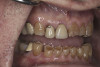

(7.) Preoperative anterior, open view. Note the significant amount of wear, erosion, and abfraction lesions.

Figure 7

(10.) Preoperative anterior, closed view. Note the end-to-end occlusion of the anterior teeth and the wear on the incisors and centrals resulting in no anterior or canine guidance.

Figure 10